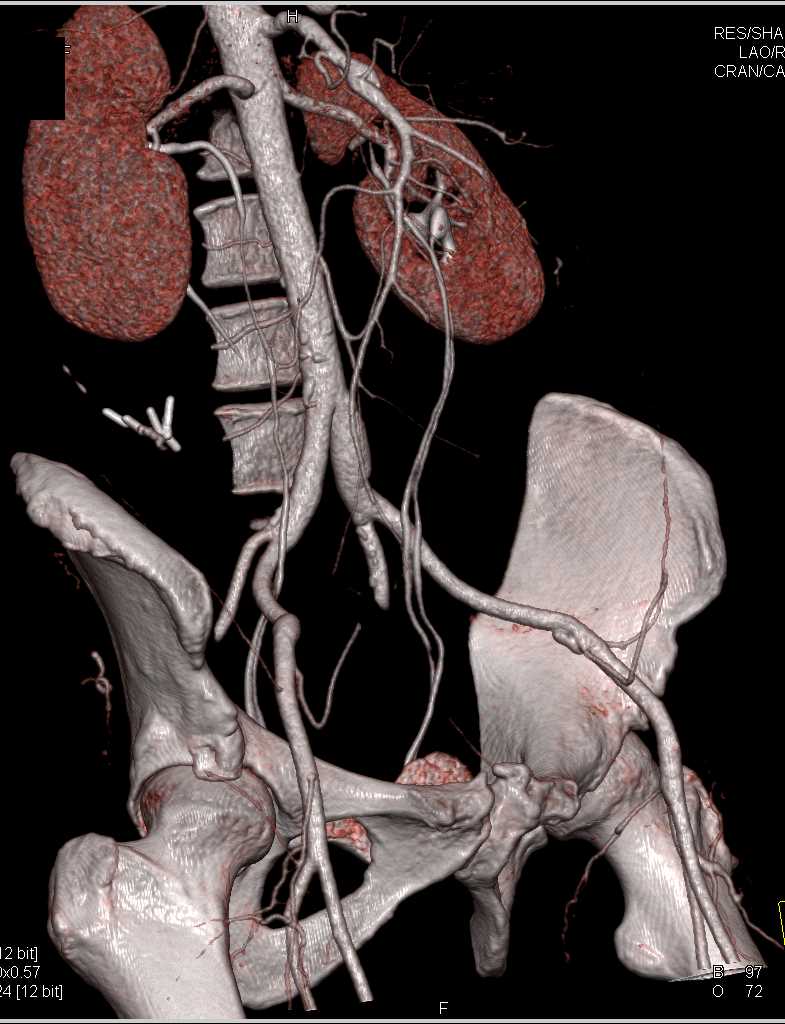

SMA Stenosis